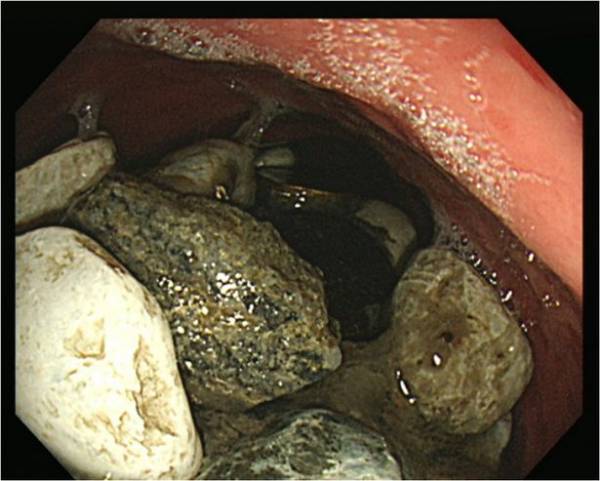

پزشکان سنگ، سر بطری و سکه را از بدن مردی که آن ها را برای درمان اضطرابش می خورد، بیرون کشیدند. مرد 54 ساله ای در بیمارستان بستری شده است و از درد شدید معده و باد کردگی رنج می برد. پزشکان مربوطه تعدادی از آزمایش ها را انجام دادند تا ببینند علت دردهای او چه چیزهایی می توانند باشند. آن ها متوجه شدند که وقتی شکم او را لمس می کنند چیزی شبیه سنگ های کوچک حس می کنند اما همین آزمایش نشان داد که یک جسمی بزرگ از اشیا، شکم بیمار را اشغال کرده است.

زمانی که یک توده حاوی ده ها شی خارجی پیدا شد، پزشکان به طور عجیبی تعجب کردند. مجموعه ای از سنگ ها، درپوش بطری و سکه ها به وزن 2 کیلوگرم را از معده اش بیرون کشیده شدند؛ این مورد بسیار غیر معمول، توسط دکتر پیونگ وا در ژورنال آمریکایی گزارش های پزشکی منتشر شد.

این مرد که گمان می رود اهل گویانگ - شمال پایتخت سیول و نزدیک مرز کره شمالی است - با یک معلولیت ذهنی به دنیا آمده است. در ابتدا جراحان سعی کردند اشیا را با استفاده از گاستروسکوپی بیرون بکشند، که در آن یک لوله باریک از طریق دهان وارد شکم می شود. در این میان، در بزرگسالان سالم، اشیا قورت داده شده و شامل استخوان ماهی و مرغ می شوند. دکتر چوئی نوشت:" هنگامی که اجسام خارجی از طریق مری عبور می کند، علائم مربوط به آن نادر است. " در این مورد، با وجود اینکه بیمار از استفراغ شکایت نکرده است، اما تعداد زیادی سکه در معده او باعث درد شکمی شده است."